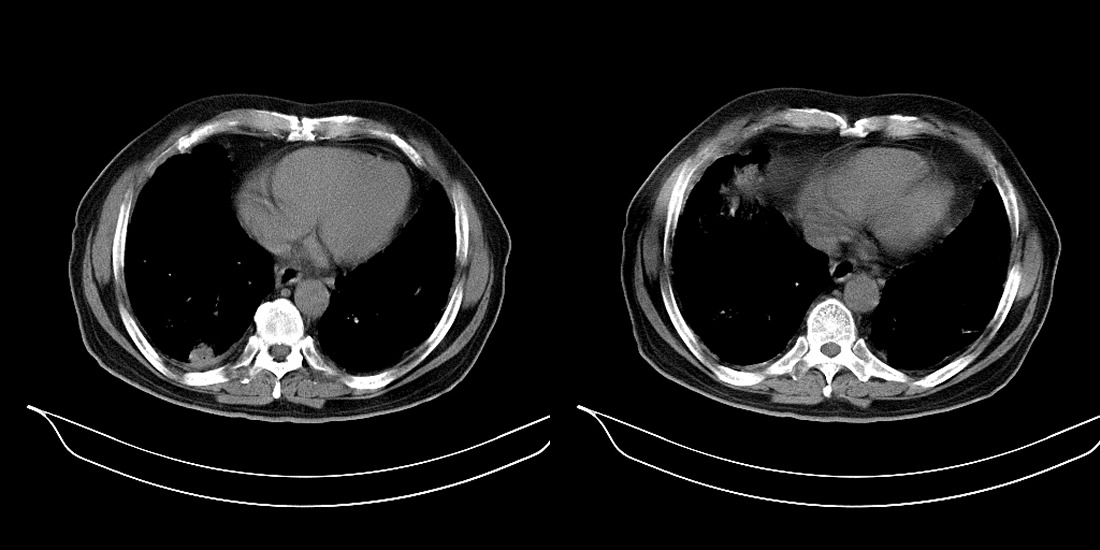

以下是引用zsl6918在2008-2-14 12:15:00的发言:[br]慢支并感染,肺气肿,肺间质纤维化,肺动脉高压。

以下是引用liuyue在2008-2-14 17:25:00的发言:[br]慢支并感染,肺气肿,肺间质纤维化,肺动脉高压 .肺大泡.[br]

以下是引用随光逐影在2008-2-15 11:10:00的发言:[br]1)慢性支气管炎并肺部感染。2)肺间质纤维化。3)肺气肿(多发性肺大泡形成)。4)肺动脉高压。